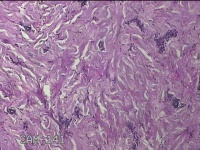

右前臂纹身

性别

男

年龄

22岁

临床诊断

纹身

一般病史

右前臂纹身切除。

标本名称

大体所见

灰白粉红色皮肤样组织6.5x0.8x0.3cm一块,表面糜烂,切面灰白粉红色,质软。

图1

慢性炎,瘢痕组织增生。